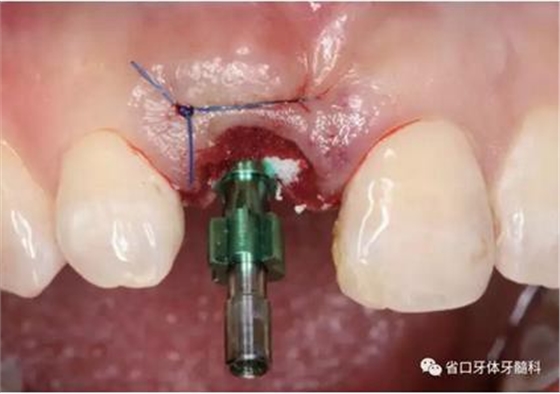

(2)制備臨時冠:術(shù)后當(dāng)天取模轉(zhuǎn)移,送工廠以Zimmer®多功能 攜帶體為臨時基臺制備臨時修復(fù),獲得舌隆突開孔螺絲固位的烤塑臨時 冠。將其就位于口內(nèi)種植體,調(diào)整正中、前伸及側(cè)方咬合無接觸,加力 10~15N·cm,可見即刻修復(fù)體良好地支持齦緣及牙齦乳頭結(jié)構(gòu)。

圖21 烤塑臨時冠

圖22 臨時冠就位前袖口檢查

圖23 就位臨時冠